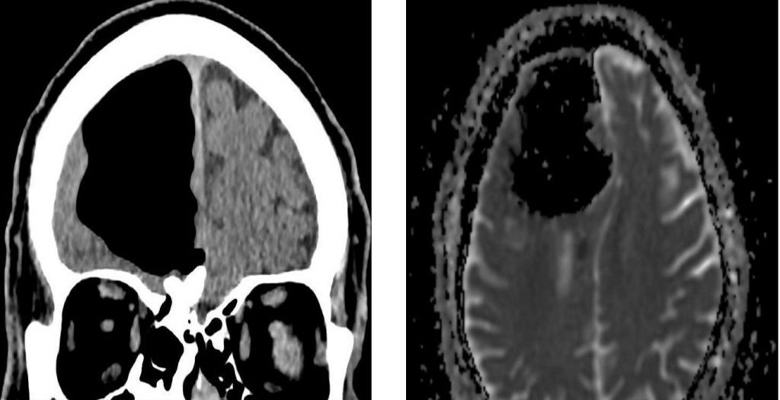

Pohjois-Irlannin lääkärit hämmästyivät tutkiessaan äskettäin 84-vuotias potilas, joka tuli heidän luokseen pahoinvoinnilla. Tehtyään miehen pään magneettikuvauskuvauksen lääkärit huomasi yllättäen, että hän puuttui osasta oikeaa etuosaa aivojen lohko. Sen sijaan eläkeläisen kallo oli ilmaa taskussa. Sitten lääkärit päättivät, että todellinen aivojen fragmentti potilas ei hävinnyt mihinkään, mutta häntä sekoitettiin tämän epänormaalin suuntaan onkalo.

Sairaalan henkilökunta ehdotti potilaan käyttäytymistä vaikeana toimenpide ilmataskun poistamiseksi, mutta mies kieltäytyi leikkauksesta. Eläkeläisen mukaan hänen ikä, hän yleensä tuntuu erittäin hyvältä eikä aikoo asettaa henkensä vaaraan makaamalla skalpelin alla. K onneksi pian irlantilaisten hyvinvointi katosi ja nykyhetkessä tällä hetkellä hänellä ei ole mitään epämukavuutta, joka liittyy heidän epänormaali terveydentila.